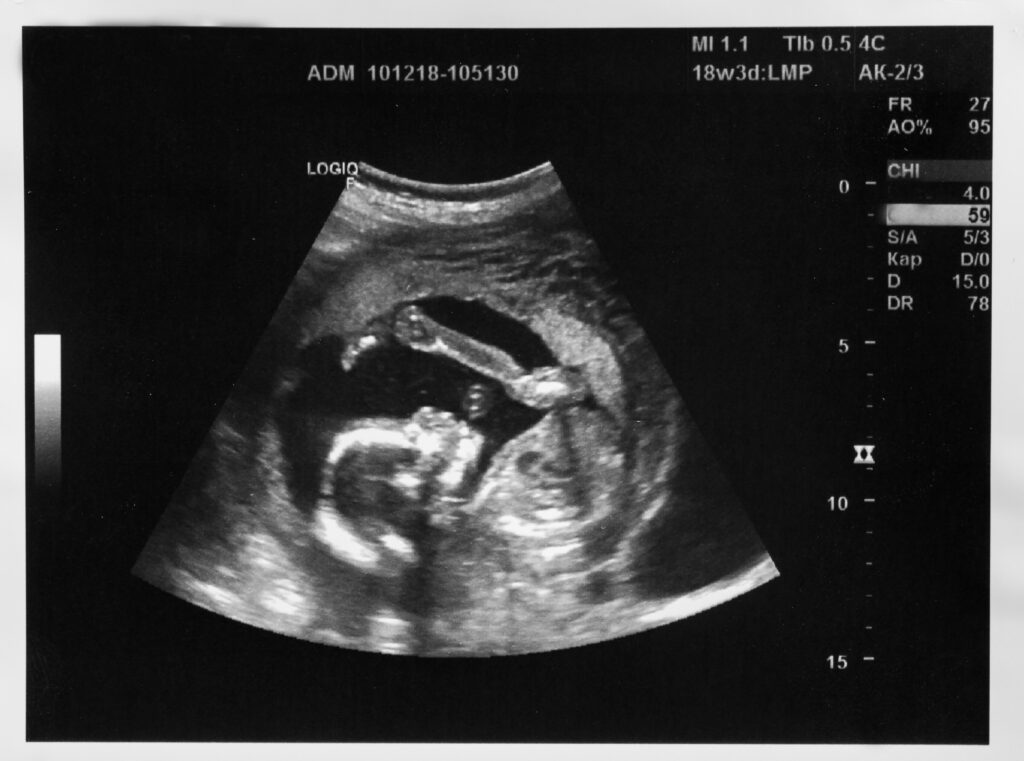

Science displays majesty in Alexander Tsiaras’ “From Conception to Birth Visualization” shared during his 2010 TED Talk. Through magnificent artistry and scientific genius, Tsiaras’ visualization embodies this year’s March for Life theme – Unique from Day One: Pro-life is Pro-science. The presentation depicts the indisputable science of the beginning of human life through its nine-month progression to birth. Fertilization takes place upon the fusion of a woman’s oocyte/egg and a man’s sperm, begetting a distinct new member of the human race with blueprints for every organ, system, and specialized cell in the body.

Tsiaras’s language is plain: Day one identifies the new member in his visualization – “24 Hours – baby’s first division,” he labels the image (found at time point 2:25.) Tsiaras notes during the 9.5-minute talk, “the magic of the mechanisms inside each genetic structure saying exactly where that nerve cell should go — the complexity of these mathematical models is beyond human comprehension. Even though I am a mathematician, I look at this with the marvel of how do these instruction sets not make these mistakes as they build what is us. It’s a mystery, it’s magic, it’s divinity.” He goes on to detail the human heart’s early development and functioning at days 25 through 30, “developing at, you know, one million cells per second at four weeks…”